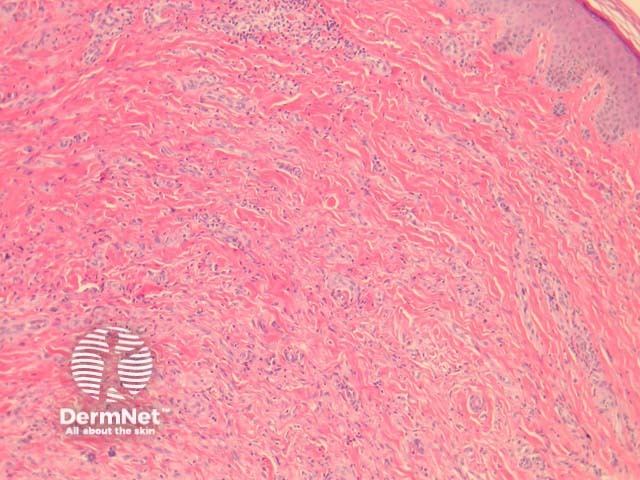

In multinucleate cell angiohistiocytoma, sections show abundant small dilated blood vessels and fibroplasia, principally in the mid-dermis (figure 1, 2). Higher power shows scattered bizarre cells (figures 3, 4) showing a pale basophilic cytoplasm and several nuclei arranged at the cell periphery (figure 3, arrow). A perivascular inflammatory infiltrate may also be seen.

Figure 1

Figure 2